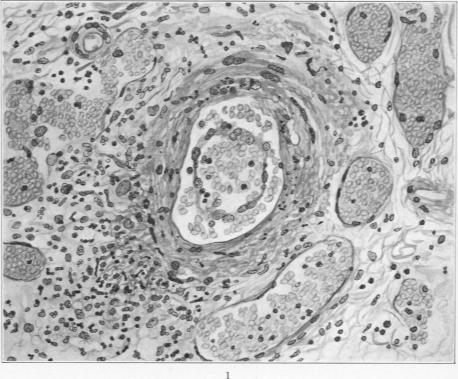

Specific Lesions of Peripheral Blood Vessels in Rheumatism.

Am J Pathol. 1926 May;2(3):235-250.11.